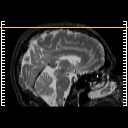

MR Study #6, March 17, 1991 -- Slice #49

[Home][Help][Clinical][Tour 1][Tour 2] Slice 49